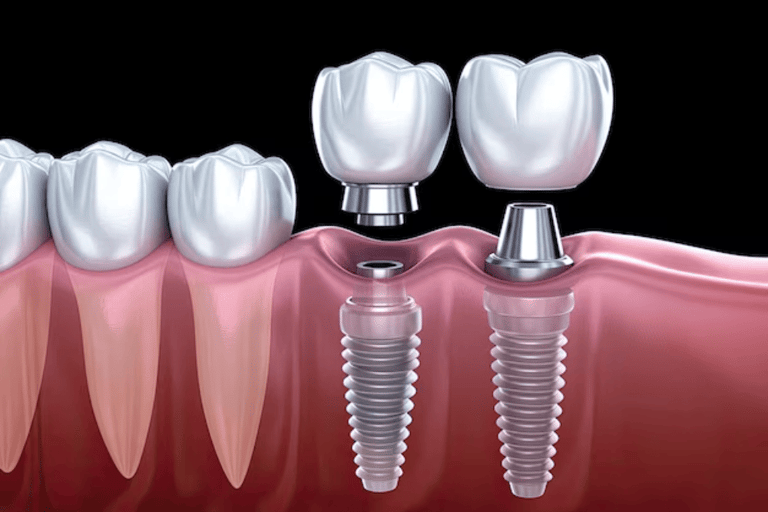

Dental Implant

Renew your smile with dental implants. Permanent, natural-looking replacements for missing teeth. Eat, speak and smile confidently again.

Implant Dentistry

Restore your smile permanently with dental implants — strong, natural-looking solutions for missing teeth and long-term oral health confidence.